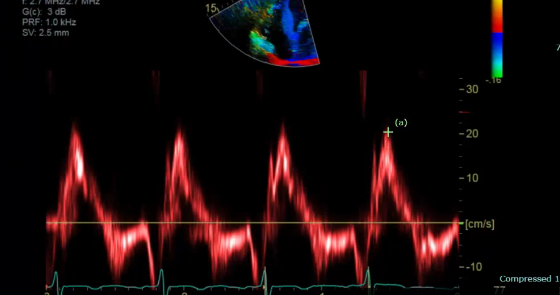

measure a TAPSE and S’ TDI

what is the TAPSE and S’ measurements

TAPSE and S’ is the longitudinal function measure how well the muscle is moving up and down

our TAPSE and S’ should match normal numbers b/c they are measuring the same thing so it should match normal

what is the measuring

This is our S’, should be >9.5